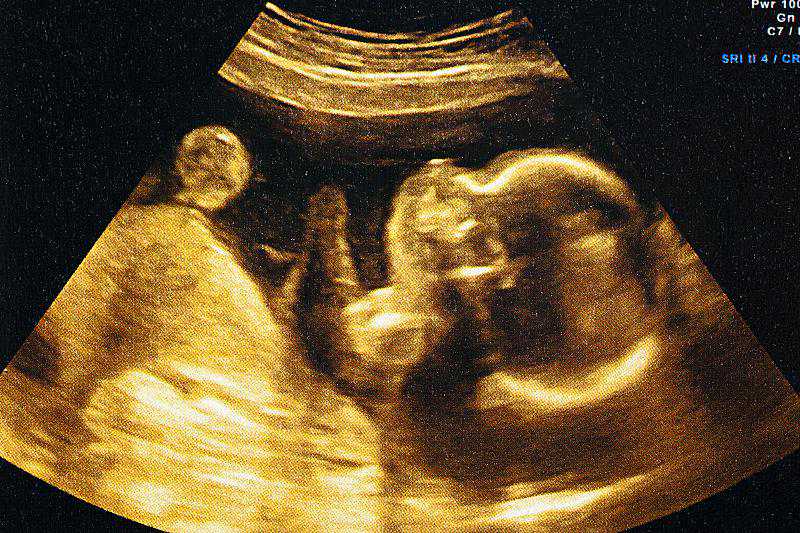

医院的三维彩超、四维彩超、无创DNA、羊水穿刺等都能帮助我们检查出宝宝是否发育正常。

早孕期检查可在10周前或11-14周去做染色体软指标、初步形态学筛查、双胎绒毛膜性判断;中孕期检查可在20-24周做系统性超声筛查;晚孕期检查可在28-34周进行补漏筛查和生长发育检查。